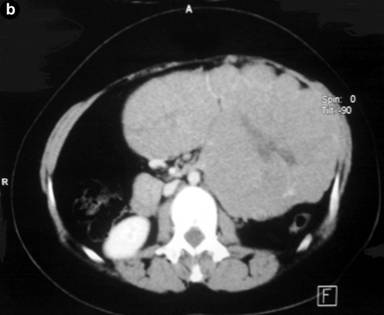

A 18-year old-female presented with progressively increasing mass in the left hypochondrium and epigastric regions of 6 months duration. There was no history of jaundice, vomiting, change in stool color, diarrhea, or flushing. On examination there was a painless, firm mass occupying the epigastric, left hypochondrium, umbilical regions which did not move with respiration. Laboratory investigations were normal, with normal serum level of CEA. Imaging in the form of ultrasonography revealed a large complex mass in the left retroperitoneum measuring 17x22x7 cm. Contrast enhanced multislice CT scan showed a large well defined mass of 17x24 cm with areas of degeneration, involving the region of the body and tail of pancreas, extending upward to the retrogastric space and downward to the level of aortic bifurcation, with no evidence of metastasis, with criteria suggestive for a solid and cystic papillary neoplasm of the pancreas (Figure 1).

Figure 1. Abdominal CT scan shows a large, well-demarcated, heterogeneous pancreatic mass. |